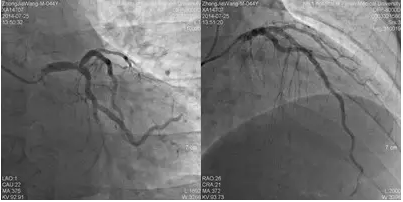

冠脉造影

造影时间:2014年07月25日。

造影前用药: 造影前给予肝素3000单位,造影中追加肝素2000单位。

造影结果(一):

造影结论及应对策略:本病例行冠脉造影发现: 右冠优势型,LM末端斑块溃疡、LAD、D未见明显狭窄,mLCX约95%狭窄,OM无明显狭窄,TIMI血流3级,见回旋支到右冠侧枝循环。mRCA闭塞。造影后向患者家属交代病情,与家属沟通后决定做介入治疗。